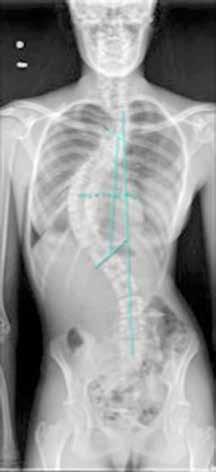

OBSTRUCCIÓN INTESTINAL ALTA TRAS CIRUGÍA DE CORRECCIÓN DE ESCOLIOSIS EN UNA PACIENTE ADOLESCENTE: UNA PRESENTACIÓN AGUDA DEL SÍNDROME DE LA ARTERIA MESENTÉRICA SUPERIOR.

Raquel Ros Briones.

Cirugía Pediátrica. Hospital Universitario de Navarra (HUN).

Arredondo Montero J., Moreno Alfonso J.C., Ugarte Mugarza L.C., Pérez Martínez A. (supervisión clínica).